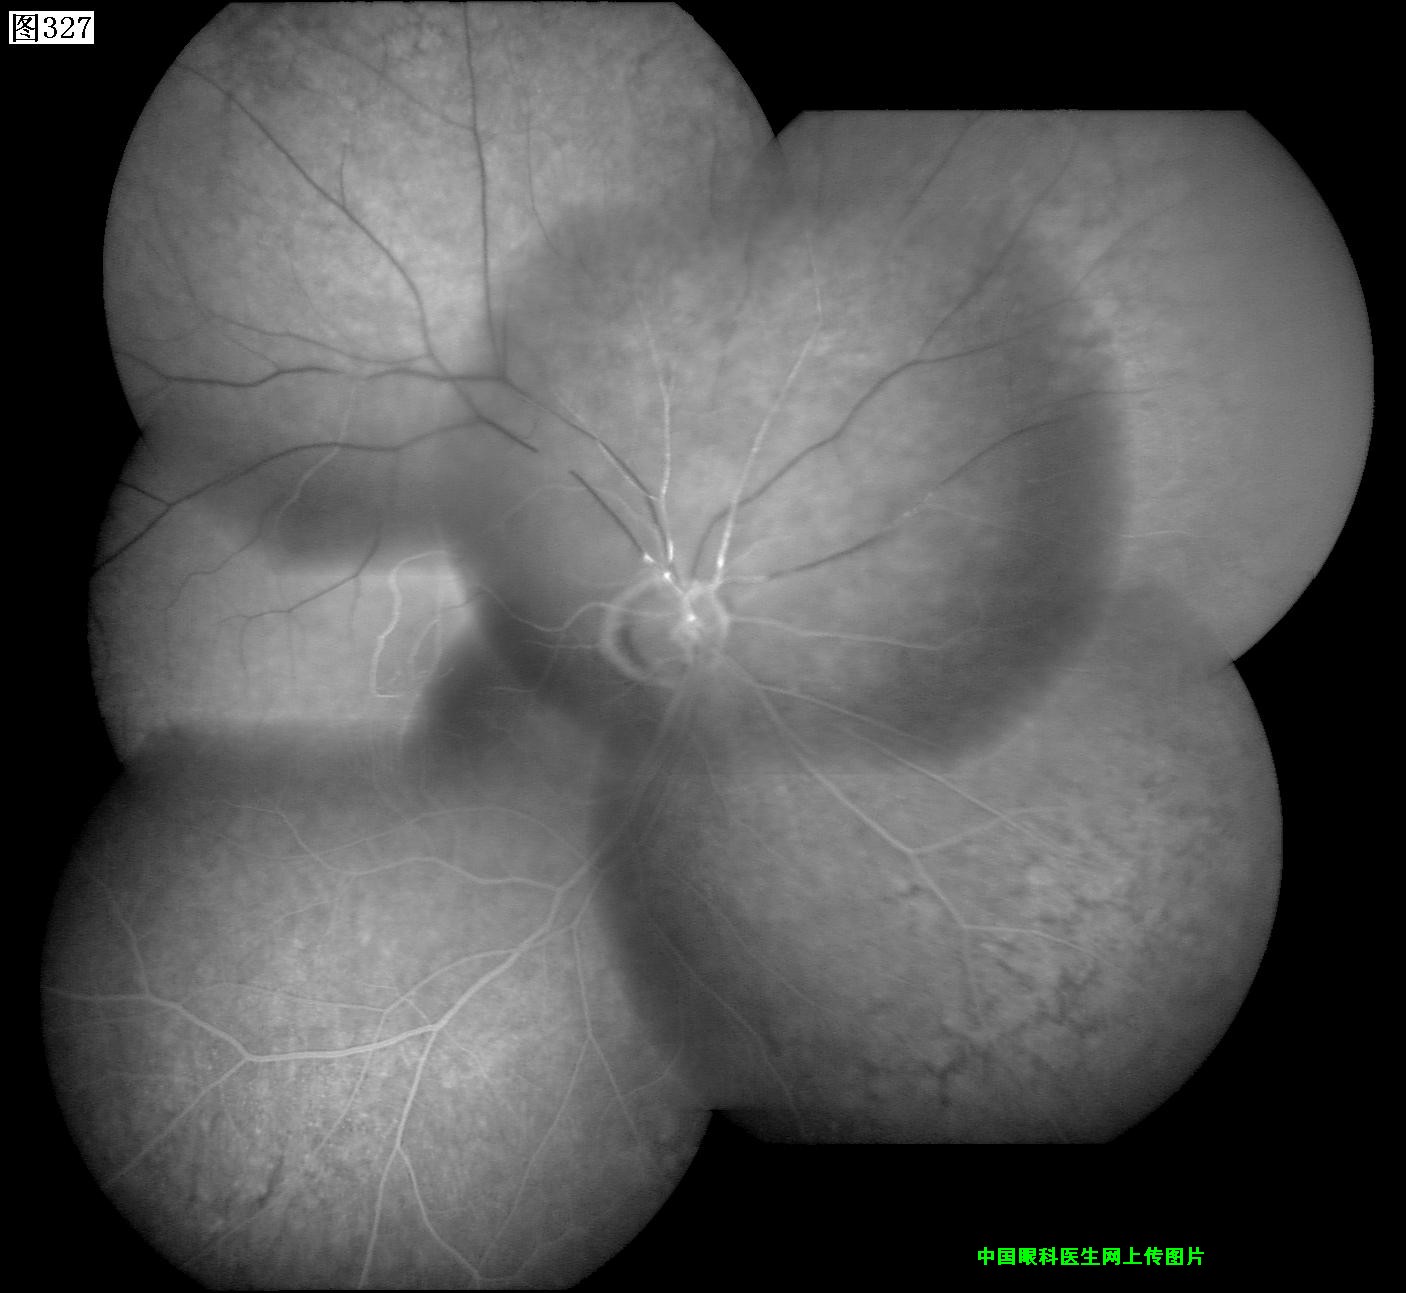

325 326 327 328